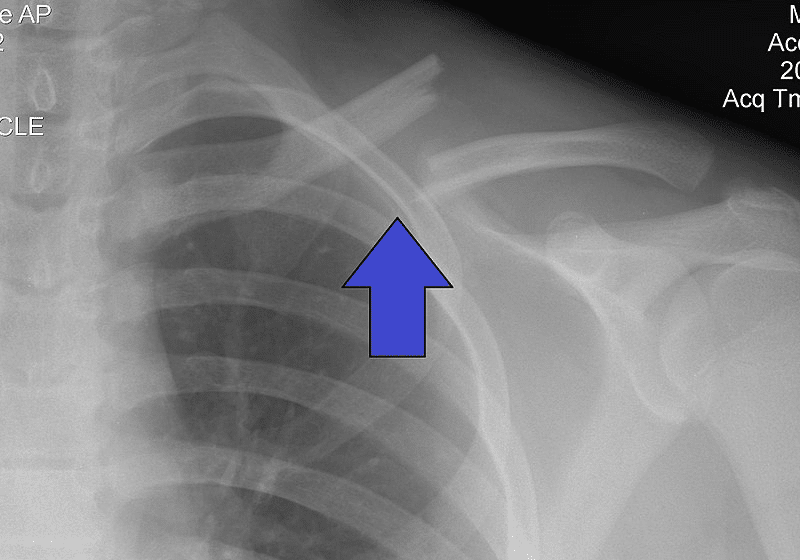

Lucie má zlomenou klíční kost. klíční kost (f.) – collarbone |